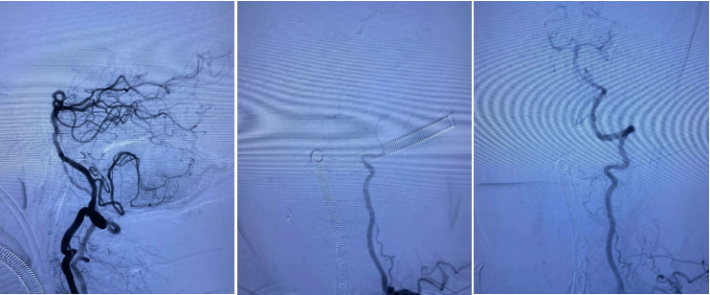

患者SCY,M59Y。2020年07月06日患者因症状性基底动脉重度狭窄,在外院行球囊扩张支架植入术。术中应用2.0mmx15mm Gateway球囊扩张,植入Enterprise 2 4.0mmx23mm支架,术后狭窄改善良好,患者无不适。规范应用双联抗血小板聚集治疗。

2020.07.10晚,患者术后第4天逐渐出现意识迷糊,嗜睡,考虑支架闭塞可能。遂急诊造影示:支架内血栓闭塞,意识模糊,危在旦夕,外院兄弟果断尝试再通,导丝导管通过后血流线样再通,撤回微导管注射替罗非班,血流难以维持。

再次尝试通过导丝导管,支架移位变形严重。

经过尝试,支架导管Rebar 18➕Synchro导丝200cm通过变形严重的原支架Enterprise 2。

打开取栓支架。

Solitaire AB 4mmx20mm成功挂住Enterprise 2。

尝试回收支架至5F Navien,牵扯力量比较大,提心吊胆。

经反复收拉尝试,最终取出Enterprise 2支架。

Enterprise 2支架在血管内两端严重变形,反折的Mark恰好被Solitaire AB支架咬合取出。

Enterprise 2支架经过体外揉搓,恢复了形态,支架内一同取出的还有一大坨增生的支架内血栓。

造影未见出血,血流良好,原狭窄在第一次支架时球囊扩张,现在狭窄已缓解。狭窄远端血管内膜稍不光滑。观察30min,血流稳定,为避免再放支架血栓,同时本次预后尚未知,暂不植入第二枚支撑支架,予以替罗非班注射液应用。